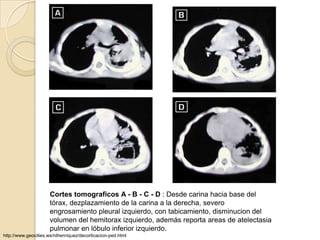

Cortes tomograficos A - B - C - D : Desde carina hacia base del

tórax, dezplazamiento de la carina a la derecha, severo

engrosamiento pleural izquierdo, con tabicamiento, disminucion del

volumen del hemitorax izquierdo, además reporta areas de atelectasia

pulmonar en lóbulo inferior izquierdo.

http://www.geocities.ws/rdhenriquez/decorticacion-ped.html